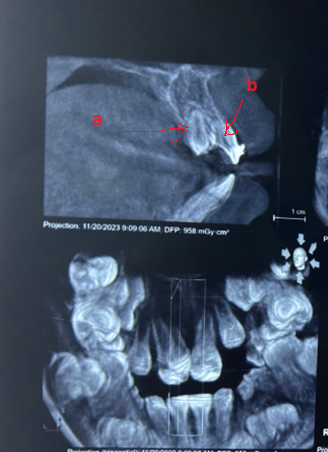

Răng thừa (b) mọc trong vòm miệng khiến cho R22 (a) mọc lệch xoay trục XQ răng toàn cảnh không thấy răng thừa do R21 (a) che khuất,(b) là R22 bị xoay trục

Hình ảnh răng thừa (a) xuất hiện rất rõ trên CT Cone Beam, (b) là hình ảnh R21

Hình 3: Tính ưu việt của CT Cone Beam trong chẩn đoán răng thừa

(Nguồn: Bệnh viện Đa khoa Tỉnh Quảng Trị)